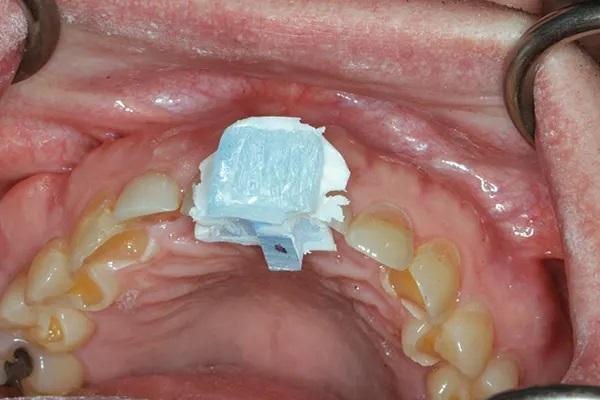

Были получены все необходимые диагностические данные, включая рентгенограммы, фотографии и цифровые сканы. Диагностика приемлемой функции позволила использовать печатную упорную пластину Lucia jig (Kois Center) вместо окклюзионного депрограмматора (Фото 7). Центрическое соотношение было легко обнаружено и зарегистрировано с помощью восковой регистрации прикуса (Фото 8). Фотографии, на которых пациент носит очки для измерения параметров лица (Kois Facial Reference Glasses, Kois Center), были использованы для цифрового монтажа и анализа случая, а также для разработки плана лечения. Резцовый край клыка верхней челюсти располагался у края верхней губы в состоянии покоя. Соответствующее положение центральных резцов верхней и нижней челюсти и задних окклюзионных плоскостей было определено с использованием принципов Центра Койса.

Фото 7: Распечатанная упорная пластина Lucia jig. Обратите внимание на темно-красную точку, обозначающую воспроизводимое положение прикуса (центральное соотношение).

Лечение стало более простым и, следовательно, приятным для лечащего врача, когда были исключены неправильный прикус и/или бруксизм, а также сопутствующие этим состояниям проблемы, и, таким образом, которые поэтому не требовали лечения. Поскольку это был случай с приемлемым функциональным состоянием, вместо окклюзионного депрограмматора была использована простая упорная пластина Lucia jig. Такой подход сэкономил время и ускорил лечение, но при этом обеспечил надежную исходную позицию для дизайна реставраций.